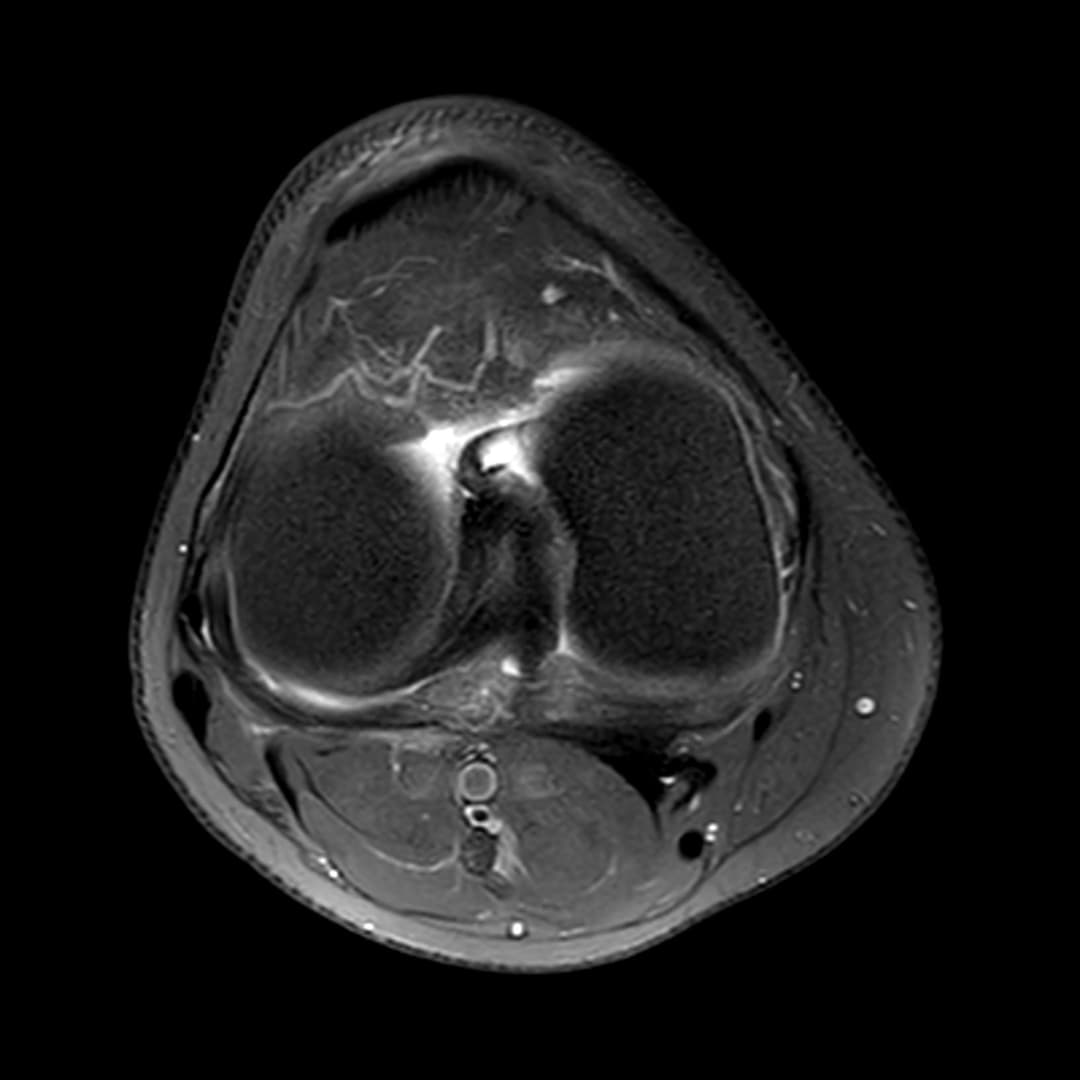

Fissure de grade 3 du segment moyen du ménisque médial.